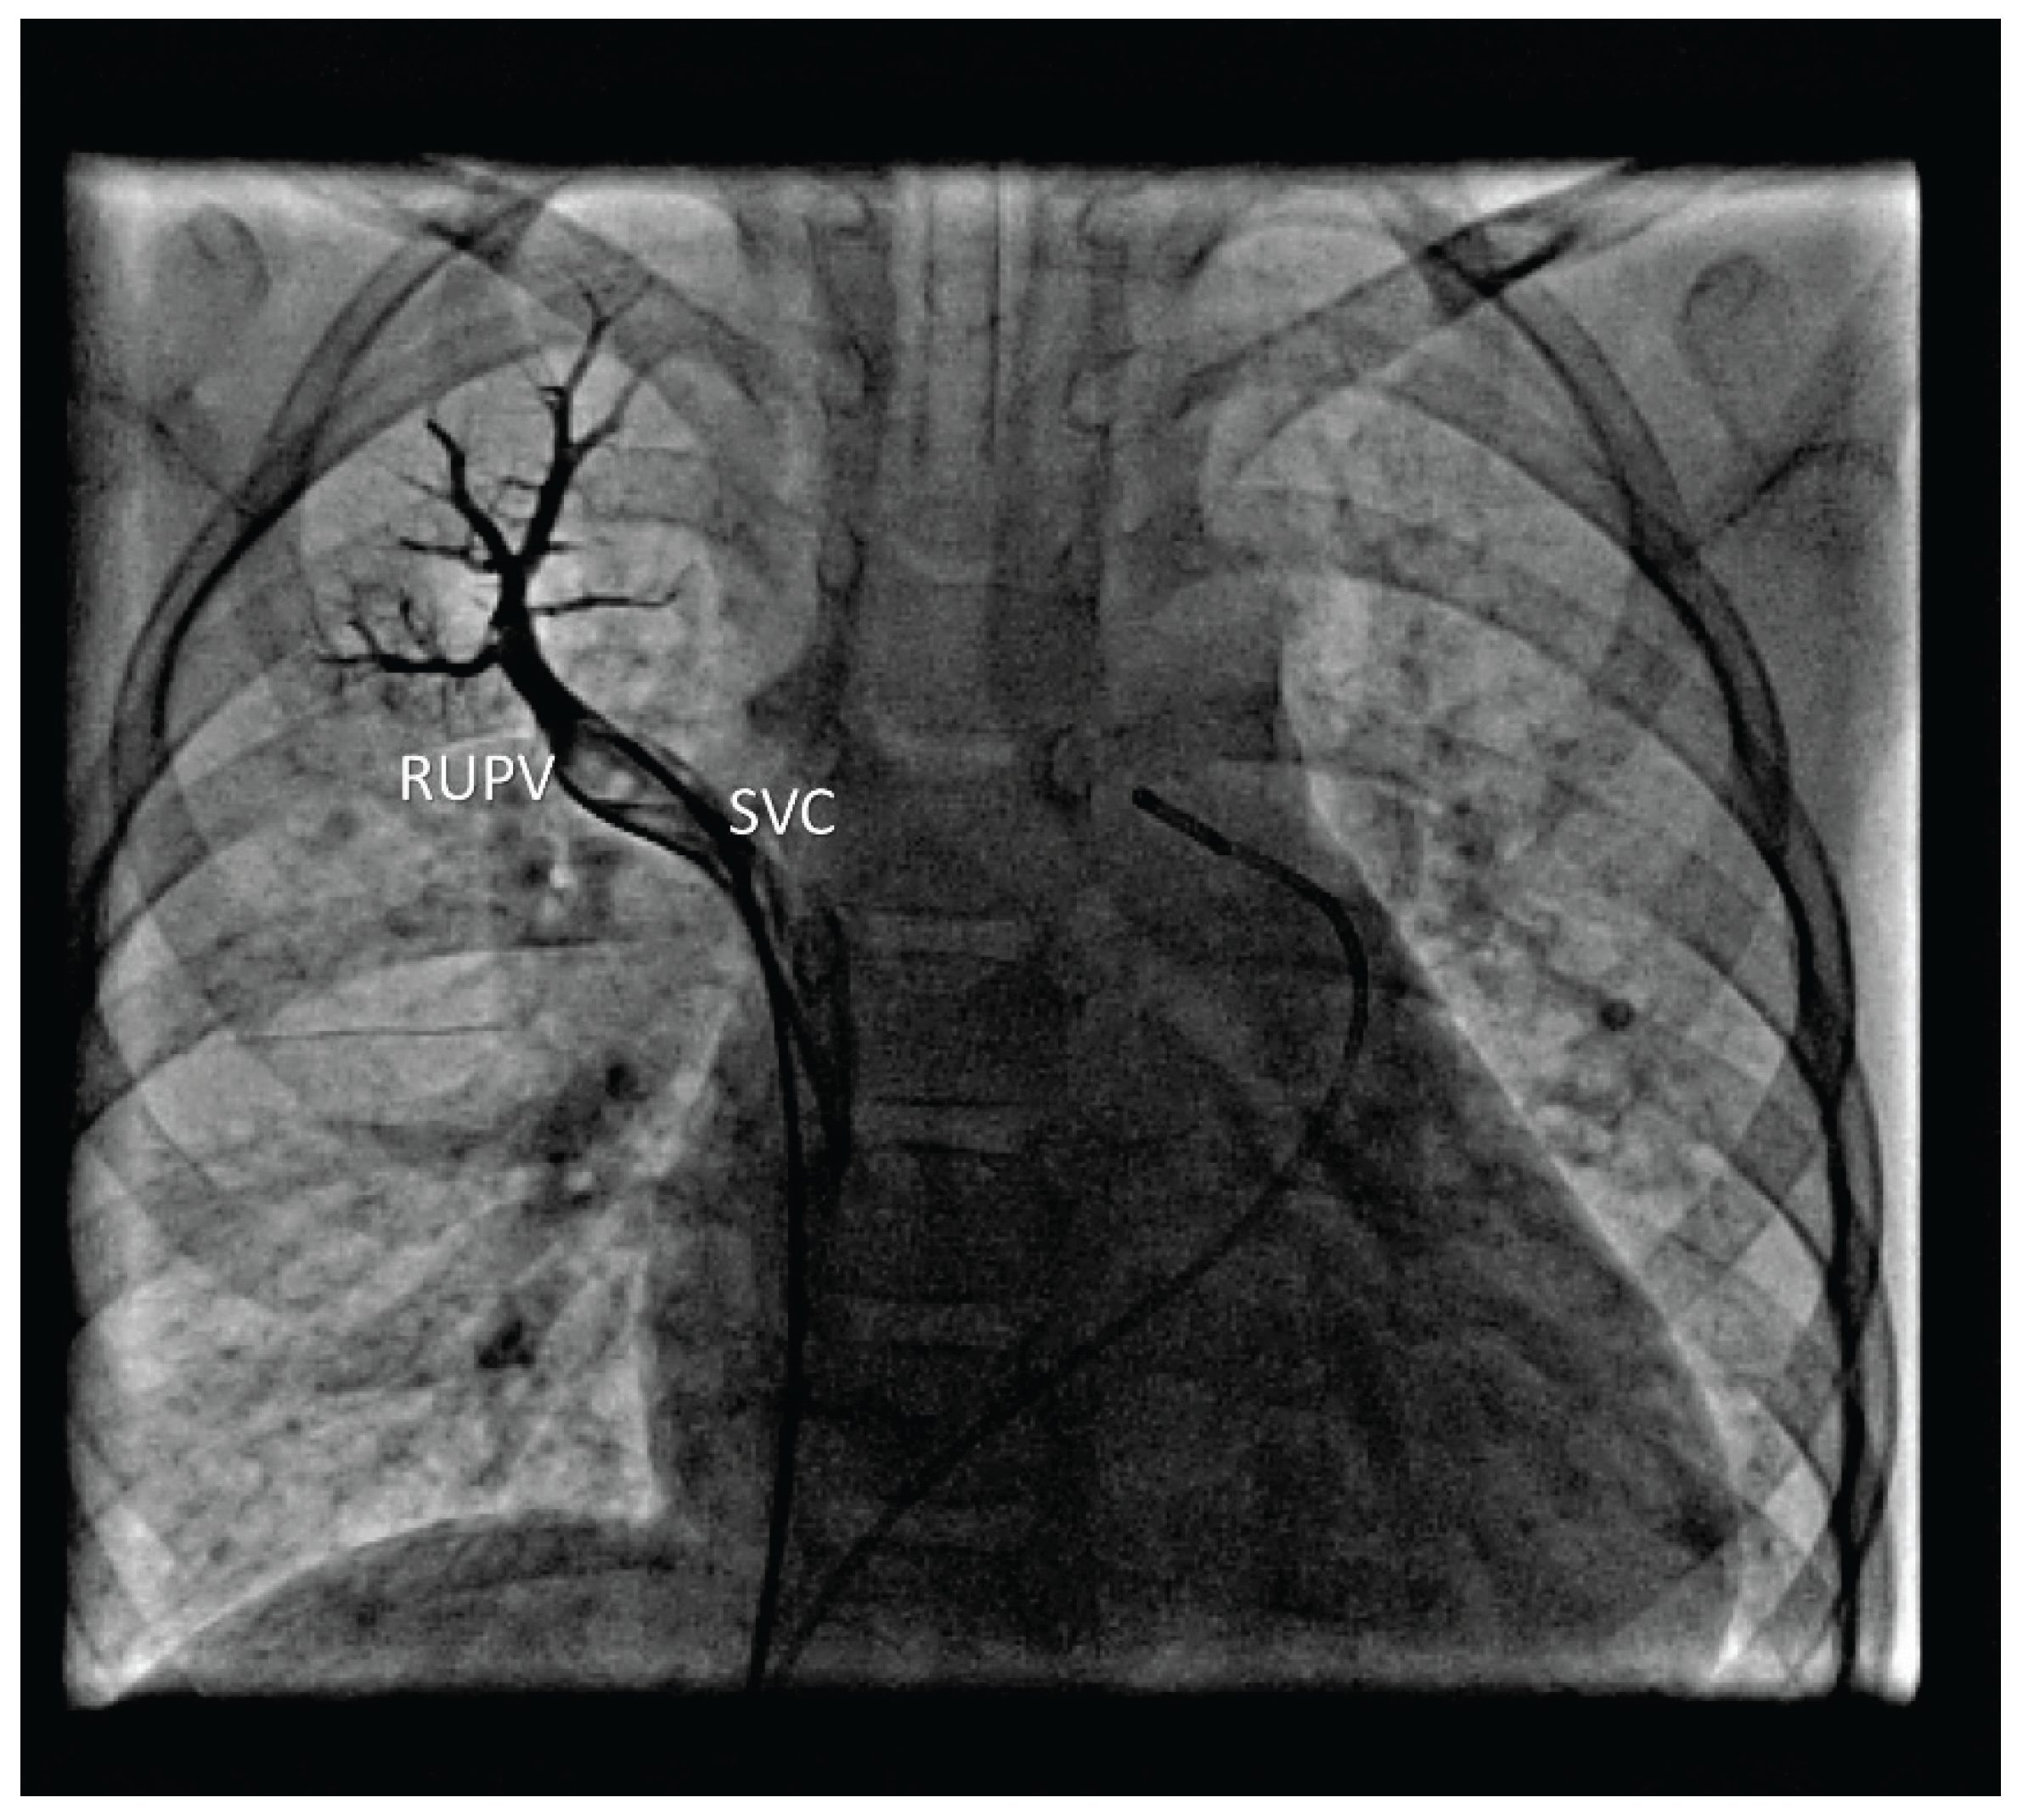

A pigtail catheter was introduced into the SVC and then advanced into a VV, when venography was performed, pressures were measured in MPA and its branches and samples for oximetry were obtained. Pulmonary angiography from the MPA showed normal arborization of the pulmonary arteries (PA). In the venous phase, anomalous pulmonary venous return was visualized and the LUPV drained via a large VV. Selective angiography of the left PA revealed normal drainage of the left lower pulmonary vein (LLPV). Selective angiography of the right PA showed anomalous drainage of the RUPV directly into the SVC, just before it entered the right atrium (Figure 1).

Figure 1. Selective venography of anomalous RUPV.